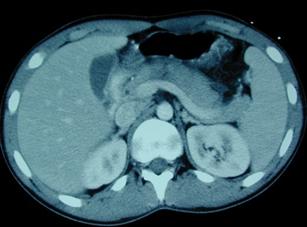

Leziune de pancreas ( ambele foto)

Traumatism abdominal

inchis

Leziune pancreatica